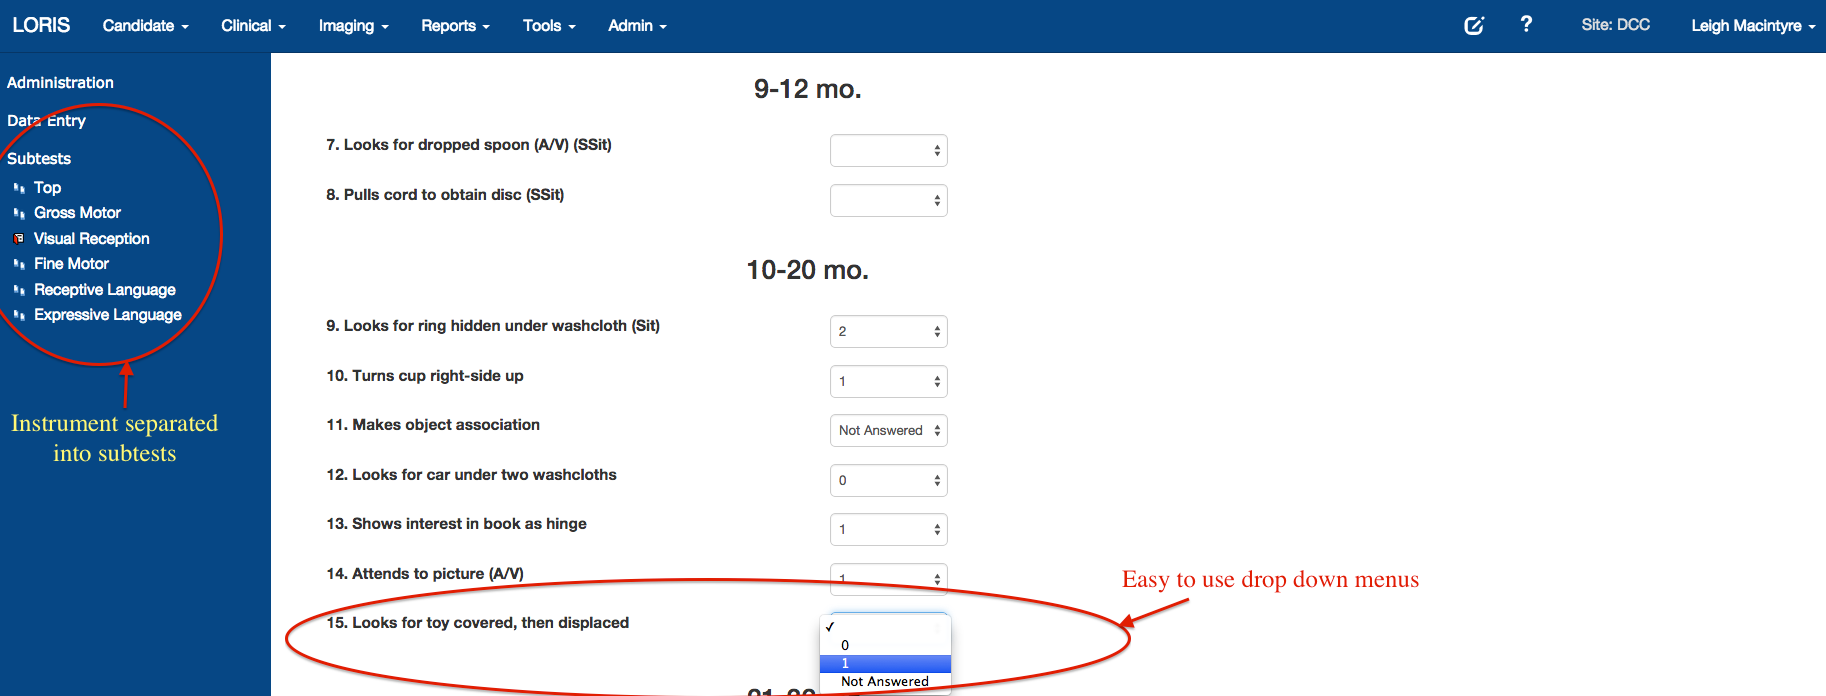

Battery of Measures

For list of 400+ instruments: https://sites.google.com/site/lorisinstrumentlist

Psychometric Data Entry

Improved Instrument Builder - New